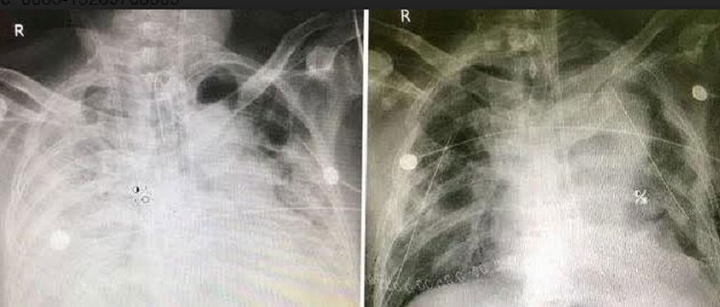

Phổi của bệnh nhân trước (phải) và sau khi ghép (trái).